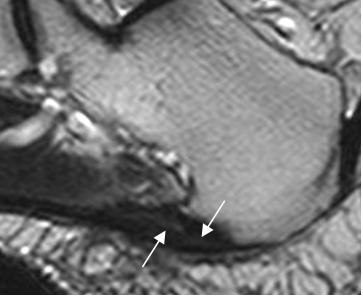

Fig 116. Fasceitis plantar.

RM sagital en T2. Fascia engrosada y con áreas hiperintensas, por cambios inflamatorios.